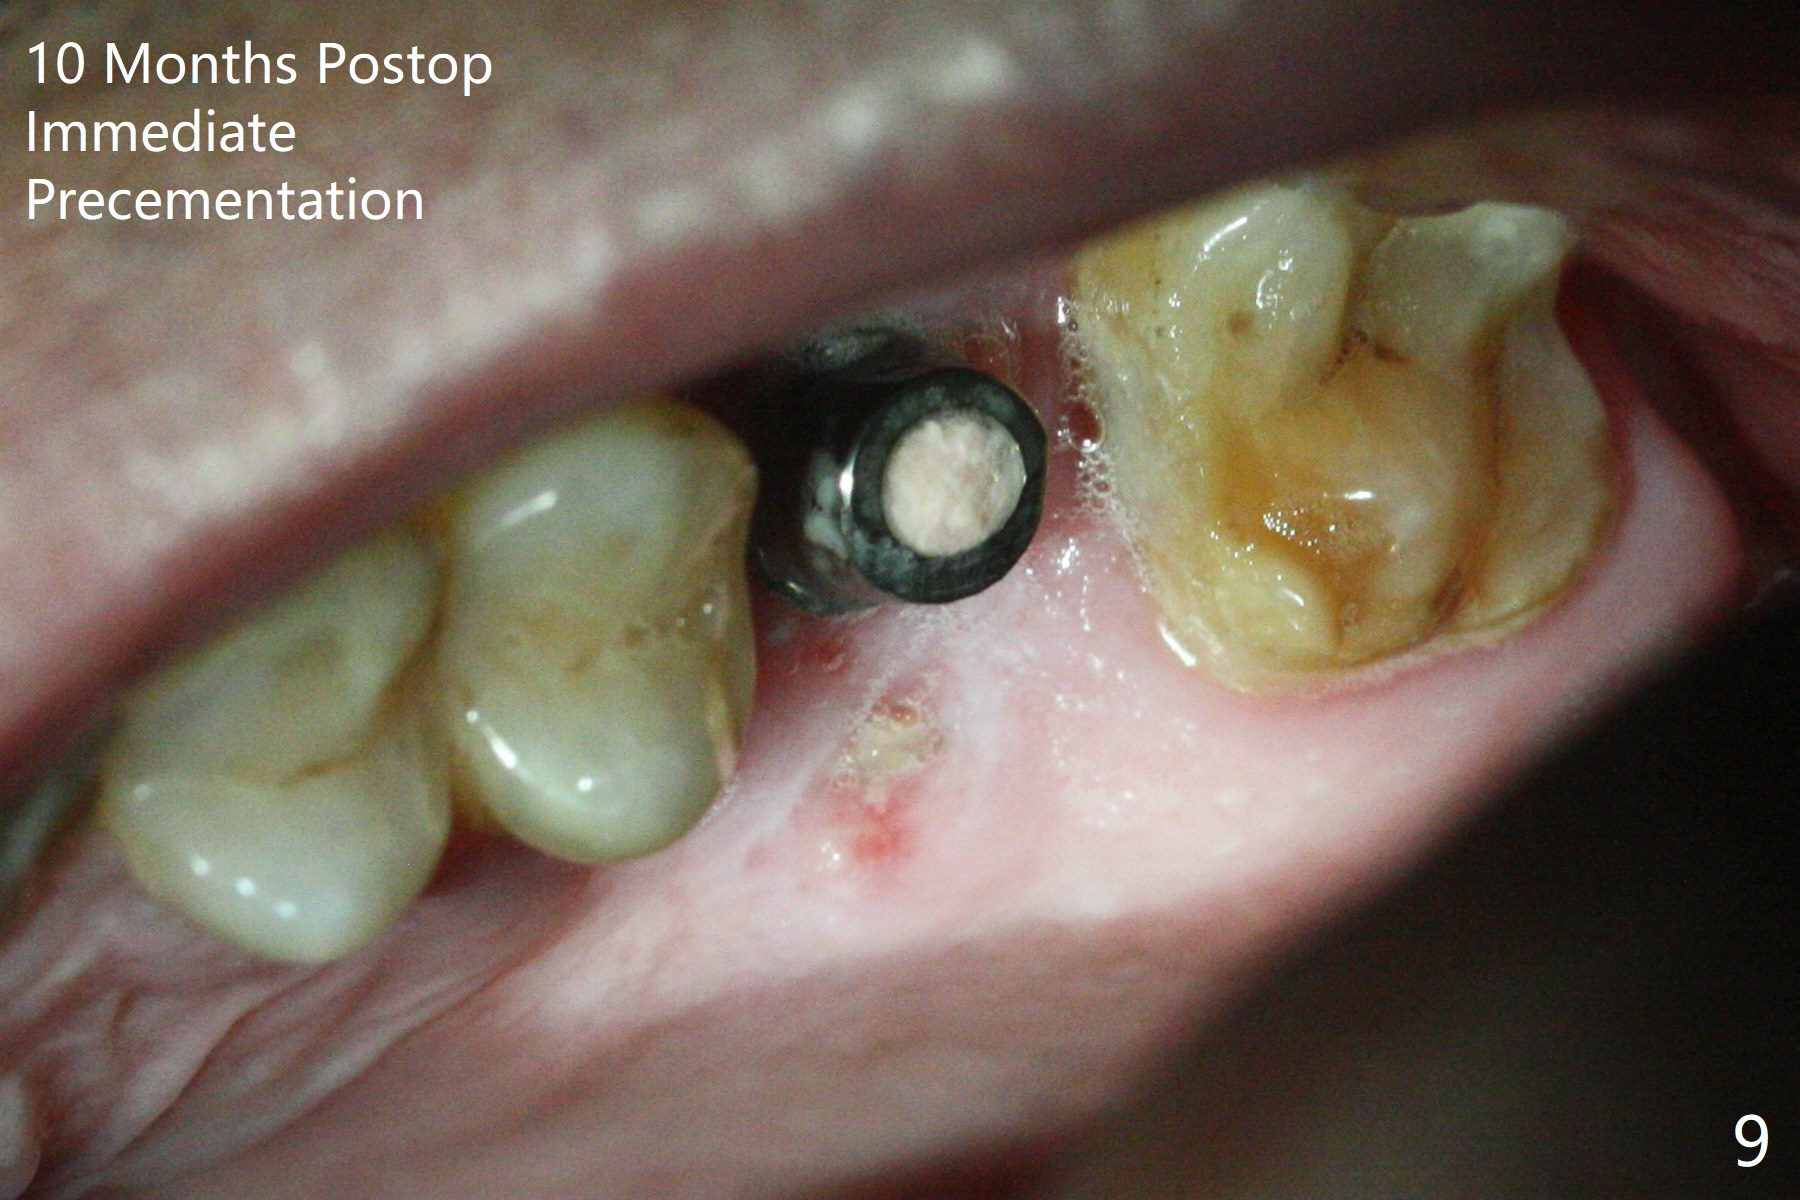

With modification of drill sequence in the last 3 steps (4.5x7.3, 4.0x8.5 and 3.5x10 mm drills) at #14 and sinus lift (Fig.1), a 5x9 mm implant is placed with ~ 50 Ncm following back up twice. Sticky bone mixed with autogenous bone (Fig.1,2 white *) is placed in the sockets before and after placement of a 6.5x5.7(2) mm abutment. Since the palatal gingival margin is recessive (Fig.3 ^), a palatal socket shield retains to prevent further recession (Fig.4 in the end of periodontal probe). Because the margin of the abutment is low, it changes to one with longer cuff (Fig.5). An immediate provisional is fabricated (Fig.6,7 P). The bone graft is indistinguishable from the original alveolus 9 months postop (Fig.8 *). The palatal socket shield is exposed 10 months postop (Fig.9 <). Since the implant is intentionally placed buccal; the sheath is not essential.